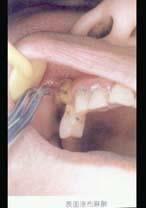

7岁患儿下颌乳中切牙松动Ⅲ度、拔除时宜采用 ( )

A2%普鲁卡因浸润麻醉

B2%丁卡因表面麻醉

C2%利多卡因浸润麻醉

D2%利多卡因阻滞麻醉

E2%普鲁卡因阻滞麻醉